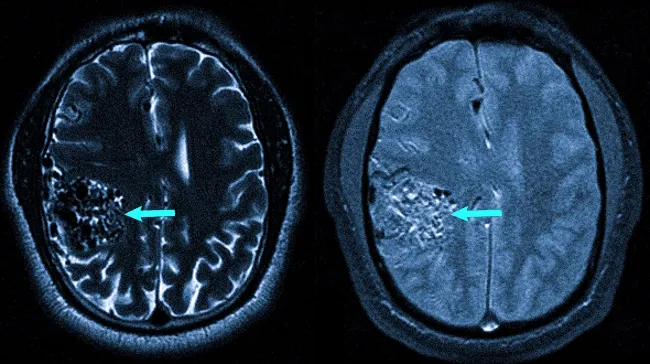

Рис. 1) Результат радиохирургического вмешательства при лечении каверномы ствола мозга. Слева — кавернозная ангиома, находящаяся на боковой поверхности ствола мозга в момент применения радиохирургии с использованием Гамма-ножа. Справа — заметное сокращение размеров каверномы спустя 3.5 года после проведенного лечения. Повторные кровоизлияния отсутствуют

На МРТ показана артерио-венозная ангиома, располагающаяся в правом полушарии мозга (обозначена стрелкой).